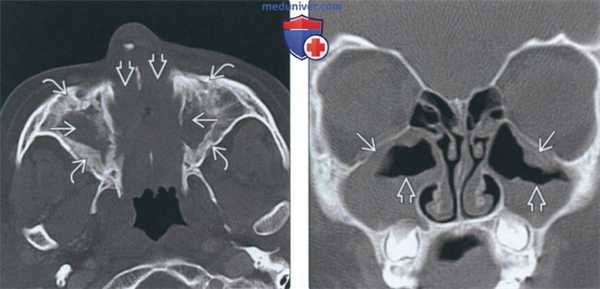

3. КТ при хроническом риносинусите:

• «Костная» КТ:

о Утолщение слизистой оболочки или снижение пневматизации пазухи без ее вздутия

о Острый синусит: уровни жидкости и газа

о Содержимое вариабельной плотности:

- Изо- или гиперденсное в зависимости от содержания белка, воды, грибкового компонента

- Гиперденсное содержимое: «выветренная» слизь или грибковый синусит

о В единичных случаях могут обнаруживаться кальцинаты

о Утолщение и склероз костных стенок пазухи (остеит)

о Ретенционные кисты, содержащие слизь, и полипы

о Тонкосрезовая аксиальная «костная» КТ с реформатированием в корональной плоскости

о Позволяет оценить утолщение слизистой оболочки, снижение пневматизации и изменения костей

• Выбор протокола:

о Аксиальная КТ с толщиной среза 0,625-1,25 мм с использованием костного алгоритма с реформатированием в сагиттальной ± корональной плоскости

• КЛКТ и КТ в костном окне

о Утолщение слизистой оболочки или снижение пневматизации пазухи без ее вздутия о Вариабельная плотность секрета:

- Изо- или гиперденсный сигнал в зависимости от наличия белка, воды, грибков

о Иногда могут присутствовать кальцинаты

о Утолщение и склероз костных стенок

5. Рекомендации по визуализации:

о Тонкосрезовая аксиальная КТ в костном окне с реформатированием в корональной плоскости

о КТ позволяет оценить отделы пазух, недоступные эндоскопически

о Аксиальная КТ в костном окне со срезами толщиной 1-1,25 мм с реформатированием в корональной ± сагиттальной плоскости